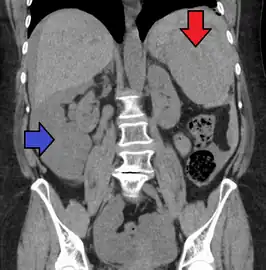

Image of abdomen shows ruptured spleen (and the perisplenic hematoma) -

Splenic hematoma resulting in free abdominal blood